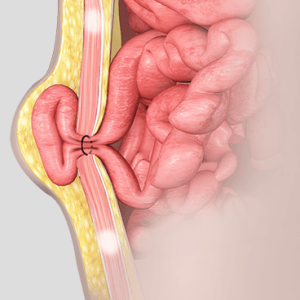

Hernia surgery

Hernia surgery is a medical procedure performed to repair a hernia, which occurs when an organ or tissue protrudes through a weak spot in the surrounding muscle or connective tissue.